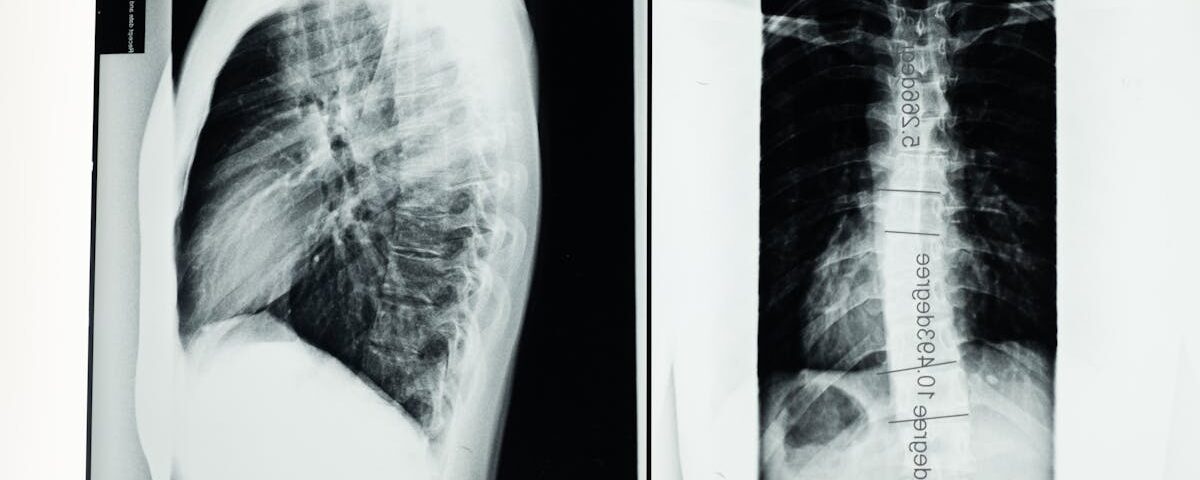

Quels examens permettent de diagnostiquer la sciatique?

Une IRM ou une radiographie est généralement nécessaire pour confirmer la cause de la sciatique.

Quels examens sont nécessaires avant de commencer un traitement de décompression pour la sciatique?

Une IRM ou une radiographie est généralement recommandée pour évaluer l’état de la colonne vertébrale.